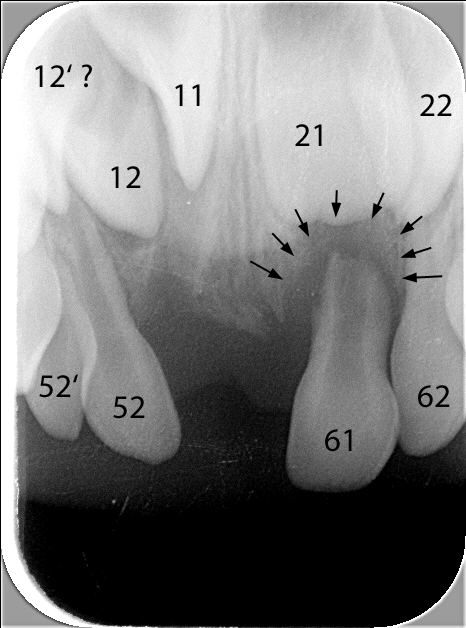

1. Vorzeitiger Verlust von zwei oberen mittleren Milch-Schneidezähnen infolge eines Sturzes (der rechte, 51, wurde direkt nach dem Sturz entfernt, der linke, 61, musste etwa 6 Monate danach entfernt werden, da sich im Knochen an der Wurzel eine Entzündung gebildet hatte). Beide Zähne sind auf dem klinischen Bild schon nicht mehr zu sehen. Die Entzündung im Knochen und die vorzeitige Auflösung der Wurzel des Zahnes 61 sind auf dem Röntgenbild 1 mit schwarzen Pfeilen markiert.

2. Überzähliger seitlicher Milch-Schneidezahn rechts (52'); siehe dazu auch den Beitrag zu überzähligen Zähnen.

3. Überzähliger bleibender seitlicher Schneidezahn (ist ein Zufallsbefund auf dem Röntgenbild).

Dieses zeigt das Standard-Oberkiefer-Front-Röntgenbild, das gemacht wurde, um die Entzündung des linken mittleren Schneidezahnes darzustellen (schwarze Pfeile). Ebenfalls ist darauf zusehen, dass der Zahn 11 (mittlerer bleibender Schneidezahn) noch etwas «verdreht» im Knochen steht, sowie der vermutete überzählige Zahn 12'.

Röntgenbild der Oberkiefer-Front mit Zahnbezeichnungen und Informationen